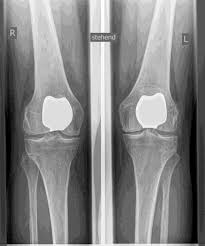

REMPLACEMENT DE L'ARTICULATION KNEAP (PFJ)

La rotule (rotule) constitue un os isolé dans une rainure du fémur et, en tant qu'articulation fémoropatellaire, représente l'un des 3 compartiments de l'articulation du genou.

Des troubles de la mobilité ou de l'instabilité ainsi que la forme de la rotule (dysplasie) peuvent entraîner des lésions du cartilage et de l'arthrose ISOLÉE DANS L'articulation fémoro-patellaire. SI LES AUTRES COMPARTIMENTS SONT EXEMPTS D'ARTHROSE, il existe la possibilité d'une arthroplastie partielle isolée de l'articulation rotulienne postérieure.